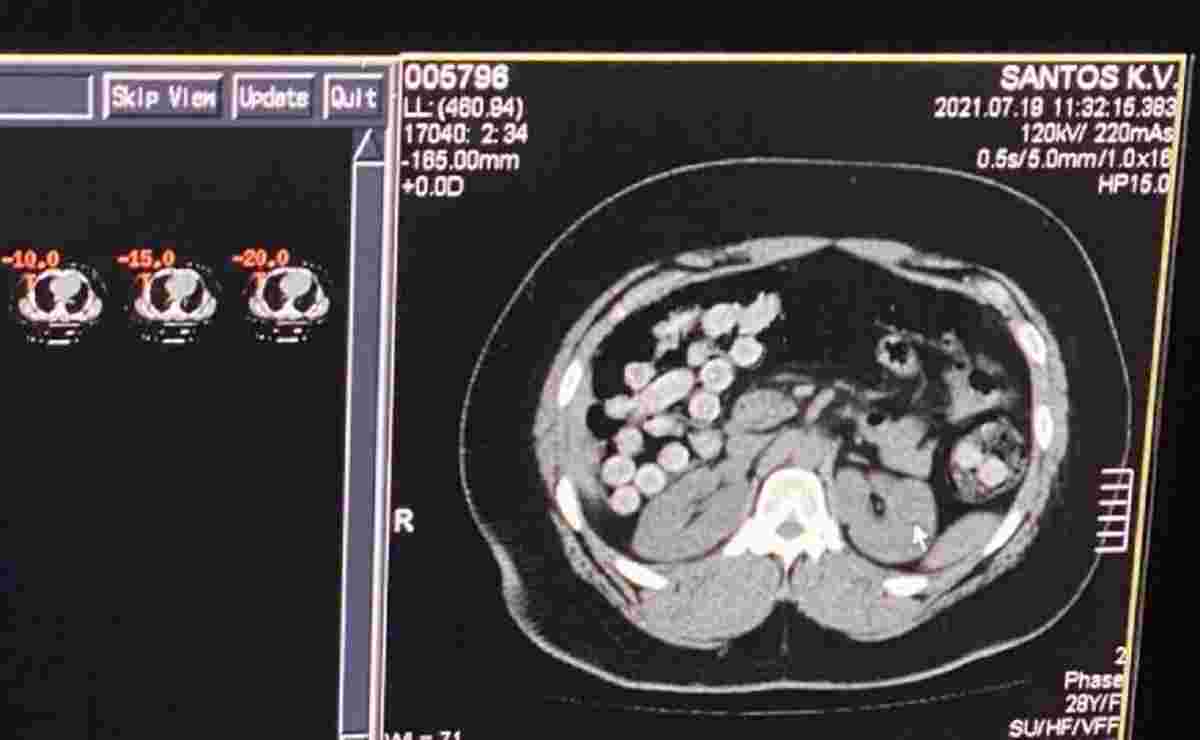

В аеропорту було затримано двох членів міжнародного злочинного угруповання з однієї з країн Латинської Америки. Правоохоронці виявили у них на двох 2 кг кокаїну. КТ показала, що в кишківнику одного з них було сховано кілька десятків пластикових капсул з кокаїном загальною вагою понад кілограм.

«Один зі зловмисників переміщував наркотики в особистих речах. Інший намагався перевезти через державний кордон понад кілограм кокаїну у кишково-шлунковому тракті», – йдеться в повідомленні.